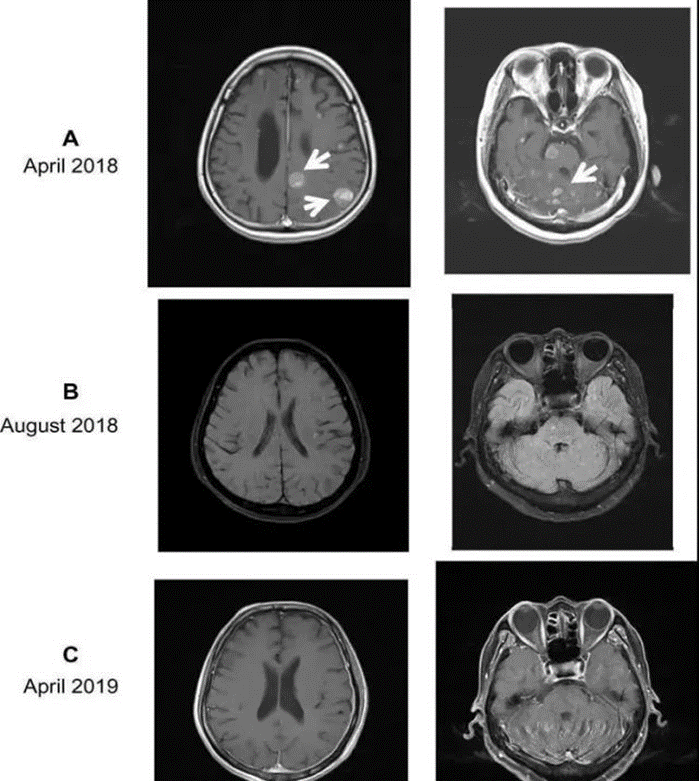

图(3)案例2:治疗前后脑部MR